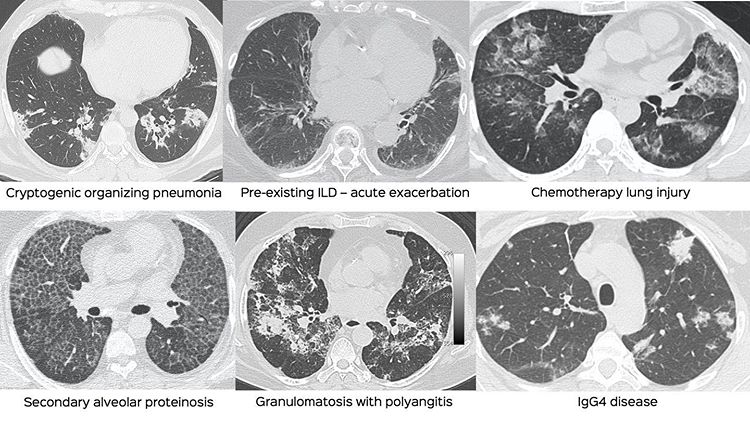

None of the findings individually seen in patients with Covid-19 pneumonia are pathognomonic, except for some of the signs of angiopathy / vasculopathy that will be shown in subsequent posts.

Organizing pneumonia patterns, crazy-paving patterns and ground glass can all occur in other situations as well, and before April 2020, we would consider all the conditions in these images in the differential diagnoses. Today in the setting of the pandemic, our first diagnosis is Covid-19, assuming that the clinical picture fits the CT scan appearance.